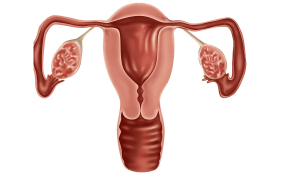

Лапароскопічне видалення маткових труб

Маткова труба (фалопієва труба) - це парний трубчастий орган, який по суті справи пов'язує порожнину матки з черевною порожниною. Основною функцією фалопієвої труби є доставка заплідненої яйцеклітини (зиготи) до місця імплантації в ендометрій, яке здійснюється за рахунок перистальтики маткових труб і ворсинок, що вистилають стінку труби. У разі наявності анатомічних змін в маткових трубах, надходження плідного яйця в матку є складним або неможливим. Часткова непрохідність маткової труби, наявність перешкод у вигляді спайок призводять до «прикріплення» зиготи в ній і розвитку позаматкової вагітності, яка може супроводжуватися небезпечною для життя внутрішньою кровотечею.